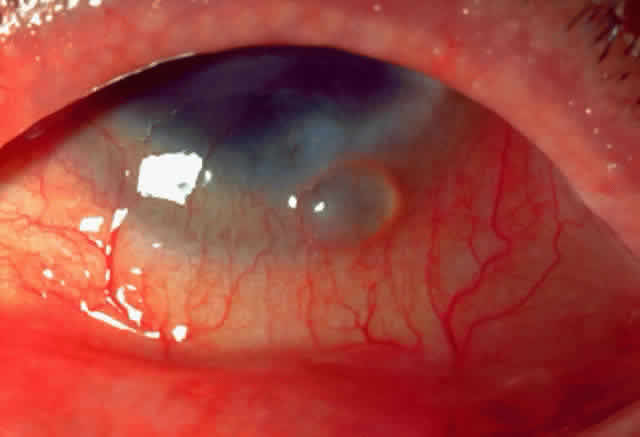

Limbal vernal begins as a thickening and opacification of the limbus. Limbal nodules appear as gelatinous, elevated lesions that may seem to coalesce and become confluent. Horner-Trantas' dots are small white elevated lesions that appear at the apices of limbal excresences that consist of desquamated epithelial cells and eosinophils (Fig. 4). Mixed vernal is a combination of limbal and palpebral lesions.